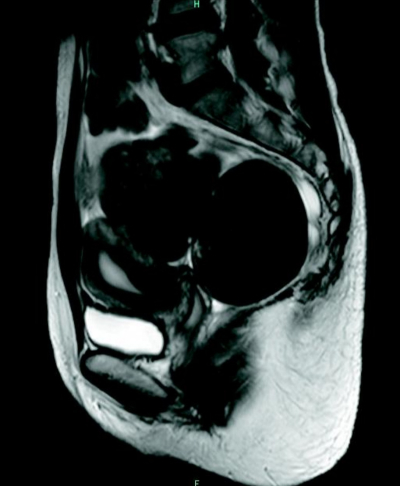

身長 162 cm、体重 58 kg。体温 36.8 ℃。脈拍 68/分、整。血圧 108/76 mmHg。心音と呼吸音とに異常を認めない。下腹部に圧痛のある腫瘤を触知する。内診では、子宮は前屈で正常大。左右付属器の腫瘤はそれぞれ径 10 cm で圧痛を認める。Douglas 窩に有痛性の硬結を触知する。下腹部 MRI の矢状断像を別に示す。

T1強調像